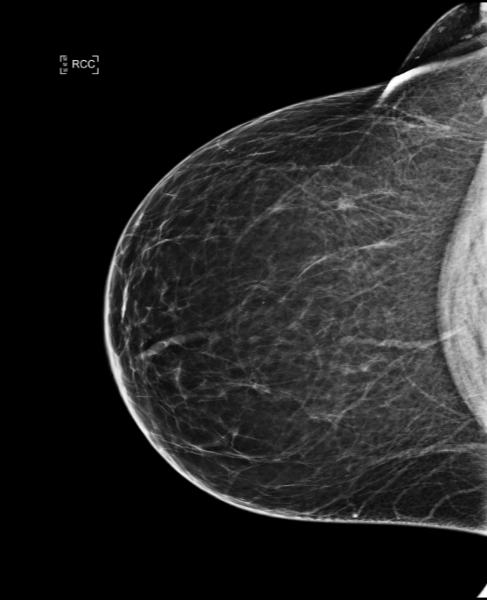

Cas de la semaine (semaine 45, 2023)

Dépistage en 2020 d’une patiente de 65 ans

Le radiologue a eu accès à un large historique d’examens antérieurs, le plus récent étant réalisé un an plus tôt. Les seins sont peu denses (densité A).

Au cours de la lecture de la mammographie, le radiologue trouve une asymétrie et une possible distorsion suspecte sur le sein droit en CC, à la fois sur la 2D et sur la tomosynthèse, sans trouver de correspondance en MLO.